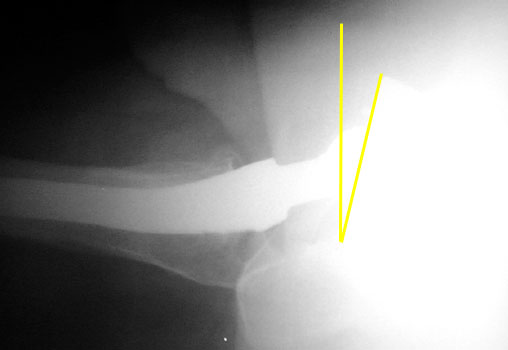

Femoral component should be anteverted. Exact degree of optimal anteversion is unknown

Femoral neck anteversion is difficult to accurately evaluate on radiographs, and can only be qualitatively assessed on a groin lateral view. This view is difficult to obtain, especially in the elderly or post operative patient, and is effected by pelvic or thigh rotation.

CT is the imaging modality of choice to evaluate for femoral neck anteversion.

Femoral neck anteversion on groin lateral film.

Version of acetabular and femoral components may be cumulative. Therefore, a retroverted cup can be compensated by an anteverted femoral component